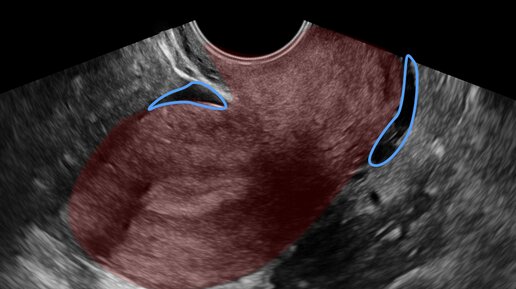

Фраза в заключении УЗИ "небольшое количество жидкости в малом тазу" всегда вызывает у женщины вопрос "откуда она там!?". После небольшого погружения будете знать ответ. Надо начать с того, что наличие небольшого количества жидкости в области малого таза – почти всегда нормально. Малый таз вмещает много органов и представляет собой динамично меняющуюся среду, где жидкость то появляется, то исчезает в зависимости от многих причин – какой день цикла, была ли овуляция, что Вы ели-пили или чем до этого занимались...

«Свободная жидкость в малом тазу», – эта фраза в заключении врача ультразвуковой диагностики для многих женщин звучит пугающе. Если доктор еще и не объяснил ее значение, то пациентка обычно обращается за информацией к «доктору-интернету». Там она находит статьи о том, что жидкость в животе – это асцит. Дальнейшие поиски информации часто приводят на сайты онкологических клиник, где асцит описывается как одно из проявлений рака. В итоге паническое состояние практически гарантировано. На самом деле жидкость в малом тазу может появиться из-за разных причин, и далеко не все они так страшны...